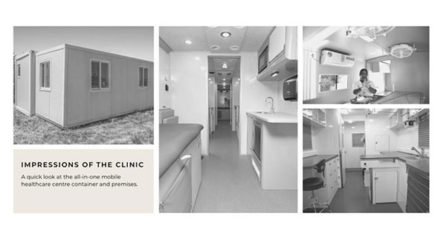

Harley Street Clinics of London is developing community-embedded primary healthcare infrastructure across rural India

Hyderabad (Telangana) [India], February 15 (ANI/India PR Distribution): Getting access to healthcare is still a distant dream for most Indian villages